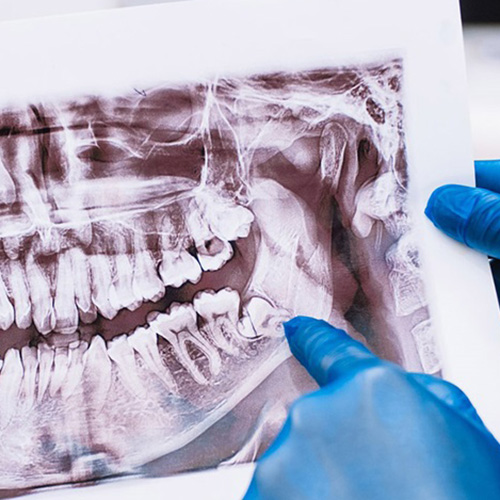

Routine Dental X-rays Reveal a Problem

Even if you feel no pain, X-rays can show hidden issues like impaction or damage to nearby teeth

At Midtown Dental, our doctors are highly experienced in managing a range of wisdom tooth concerns. In complex cases, we may recommend a 3D x-ray to accurately assess the position of the teeth and surrounding structures before proceeding with treatment.